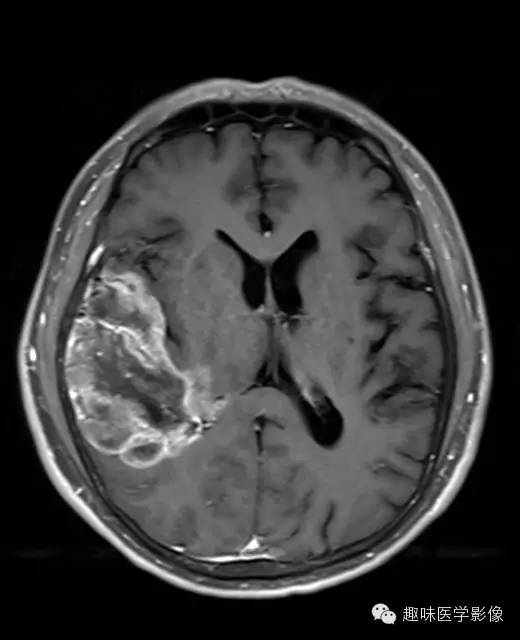

右侧颞顶叶、丘脑可见大片不规则异常信号灶,局部脑回肿胀,大小约45×75mm,T1WI呈混杂低信号,内可见多发条状高信号,中央可见更低信号灶,T2WI/FLAIR呈混杂稍高信号,内可见点状低信号,DWI呈混杂高信号,未见明显占位效应,增强后呈多发不规则花环状明显强化灶,内可见多发点状小血管影。

少突胶质细胞瘤,WHOⅡ级。

少突胶质细胞瘤为分化良好、生长缓慢但呈浸润性的肿瘤,典型者累及皮层和皮层下白质,20%-50%有侵袭性(间变性少突胶质瘤)。最佳诊断征象:部分钙化 中年人的皮层肿块,可以侵蚀并使颅骨膨胀。CT平扫为低/等密度,大部分钙化,可有出血和囊变,增强CT表现多样,从无增强到明显增强。MRI常不均匀,T1WI上相对于皮层为低/等信号,T2WI为高信号;除间变外,出血、坏死少见,边界清楚,伴轻微水肿,50%强化。